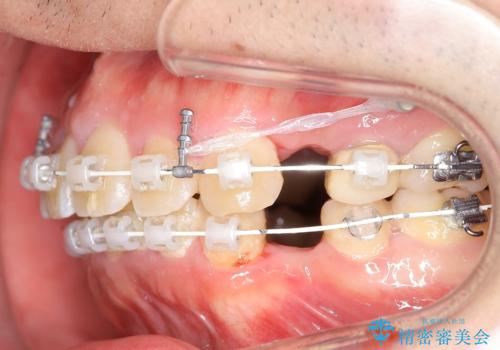

出っ歯、ガタつきの改善 ワイヤー矯正治療

- 上顎前歯の突出感と下顎前歯のガタつきが主訴で来院されました。

出っ歯とガタつきの改善を行うには抜歯が必要と診断し、上下左右第一小臼歯を抜歯する計画を立てました。

抜歯する事で歯の移動量が大きいことからワイヤー表側矯正装置で治療を行うことになりました。